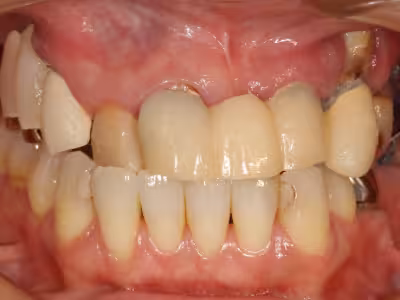

治療前後写真

治療前

治療後

40代・女性

上顎の歯が痛くて噛みにくい/見た目も気になる

治療内容

- ① CT診査・サージカルガイド作製

- ② インプラント体埋入手術+仮歯装着

- ③ 最終上部構造装着

約18 か月

3,140,500円(税込・自費診療、保険適応外)

- 術後の腫脹・疼痛・出血

- インプラントが骨結合しない可能性

- 神経損傷や上顎洞穿孔のリスク・定期メンテナンスが必要

噛む機能だけでなく口元のバランスも改善。

定期メンテナンスにより長期安定を目指します。